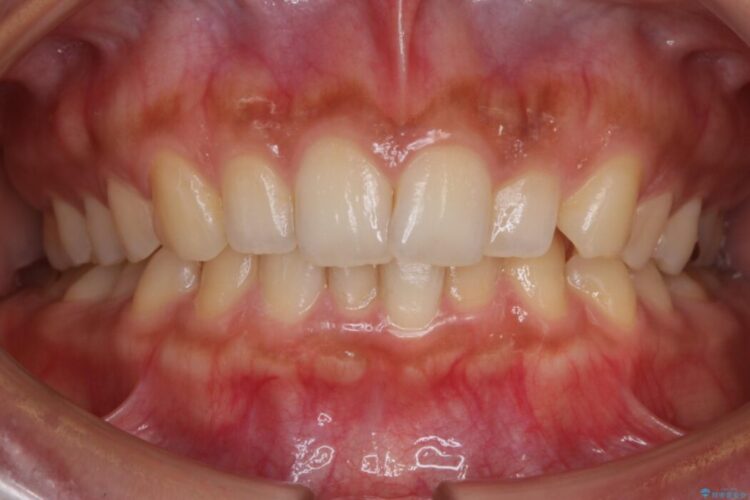

下顎前歯のガタつきを気にされて来院されました。

叢生の度合いにより抜歯は不要と判断しましたので、歯列幅の拡大を主軸に置き矯正治療を行いました。

本症例では下顎の歯列が舌側へ傾くことにより幅が狭まっていましたので、マウスピース治療により歯列弓を拡大しました。